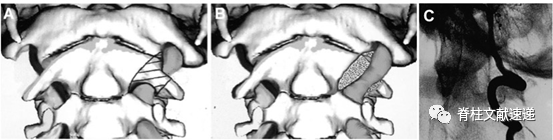

发生BHS最常见的为寰枢关节处(椎动脉V3段)。

图注:上图为寰枢椎处椎动脉V3段动态性狭窄的示意图。